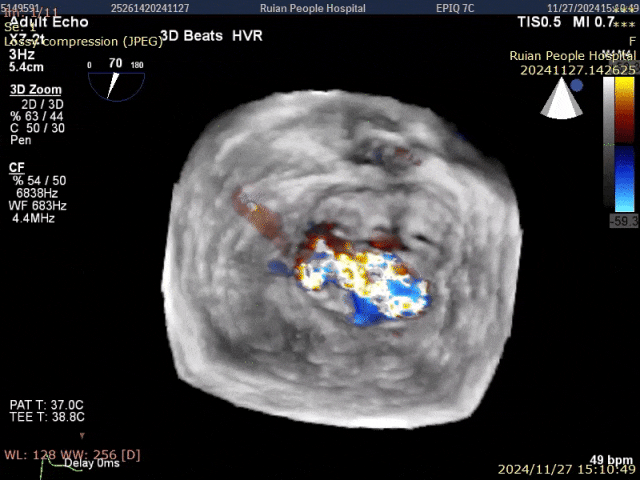

术前影像:P1脱垂伴腱索断裂,重度反流

术前3Dview

术前3D view color

术中释放前评估 3Dview color 反流微量

术中释放后评估3D view color 反流微量